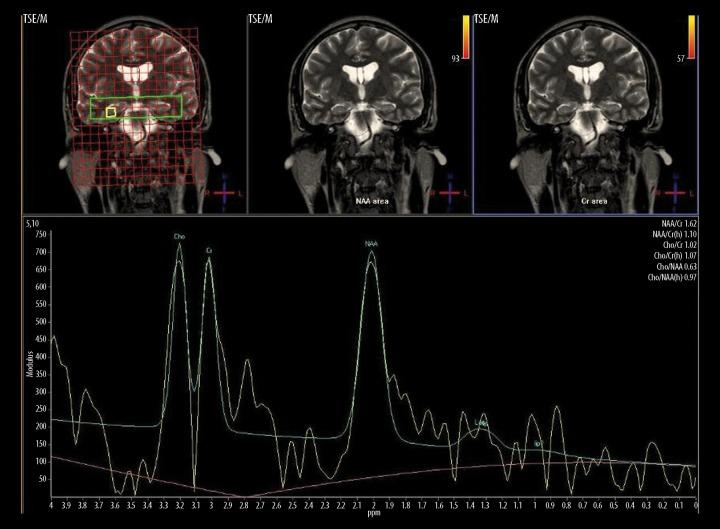

MATERIAL/METHODS: 20 OSA patients and 5 controls were included in this prospective research. MRS was performed on these 25 subjects to examine cerebral hypoxemia in specific regions (periventricular white matter and both hippocampi). Polysomnography was assumed as the gold standard. Statistical analysis was assessed by Mann-Whitney U test and Receiver operating characteristics (ROC) curve for NAA/Cho, NAA/Cr and Cho/Cr ratios.

In the periventricular white matter, NAA/Cho ratio in OSA patients was significantly lower than in the control group (p<0.05). There were no statistical differences between the OSA and the control group for NAA/Cho, NAA/Cr and Cho/Cr ratios for both hippocampal regions. Additionally, Cho/Cr ratio in the periventricular white matter region of OSA group was higher than in the control group (p<0.05).

Hypoxic impairment induced by repeated episodes of apnea leads to significant neuronal damage in OSA patients. MRS provides valuable information in the assessment of hypoxic ischemic impairment by revealing important metabolite ratios for the specific areas of the brain.